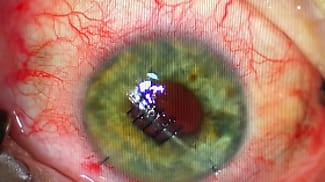

Eyecare providers can improve the quality of life of patients who have photophobia, ocular trauma, and disfiguring congenital conditions with prosthetic or tinted contact lenses.

By Jennifer Kirby